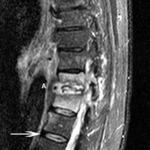

Magnetic resonance imaging of lymphoma: arrowhead indicates a soft-tissue mass protruding into the spinal canal. Arrow points to the tumor protruding anterior to the L5 vertebral body

Courtesy of Dr K. Singh; used with permission

Magnetic resonance imaging of osteomyelitis: T11-T12 disk space is involved with discitis (A). There is bony involvement of both vertebrae indicated by high T2 signal of the vertebral bodies. Arrow indicates a normal healthy vertebral disk